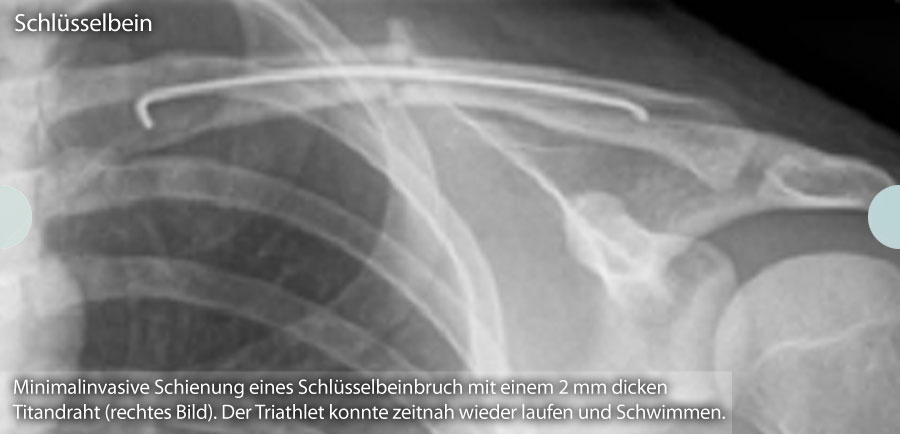

Bei Klick auf die folgenden Bilder können Sie sich diese in vollständiger Größe anzeigen lassen: